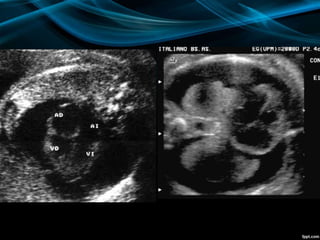

CARACTERÍSTICAS

ECOGRÁFICAS

ASCITIS

•DESDE PEQUEÑAS COLECCIONES.

•ACUMULACIONES MAYORES.

DERRAME PLEURALY O

PERICARDICO.

•UNILATERALES.

• BILATERALES.

•PEQUEÑOS.

•GRANDES.

DERRAME PLEURAL

EDEMA SUBCUTÁNEO

•GENERALIZADO.

•LOCALIZADO.

•LIMITADO A LA PARTE SUPERIOR O

INFERIOR DEL CUERPO.

EDEMA DE LA

PLACENTA

•GROSOR MAYOR A 6 CM PARA EL TERCER

TRIMESTRE

DIAGNÓSTICO

ECOGRÁFICO

PRESENCIA DE DOS O MÁS DE LOS

SIGUIENTES HALLAZGOS:

•ASCITIS FETAL

•DERRAME PLEURAL

•DERRAME PERICÁRDICO

•EDEMA SUBCUTÁNEO (MAYOR A 5 MM)

•HIGROMA QUÍSTICO

•POLIHIDRAMNIOS (50-75%)

•ENGROSAMIENTO DE LA PLACENTA

(MAYOR A 6 CM)